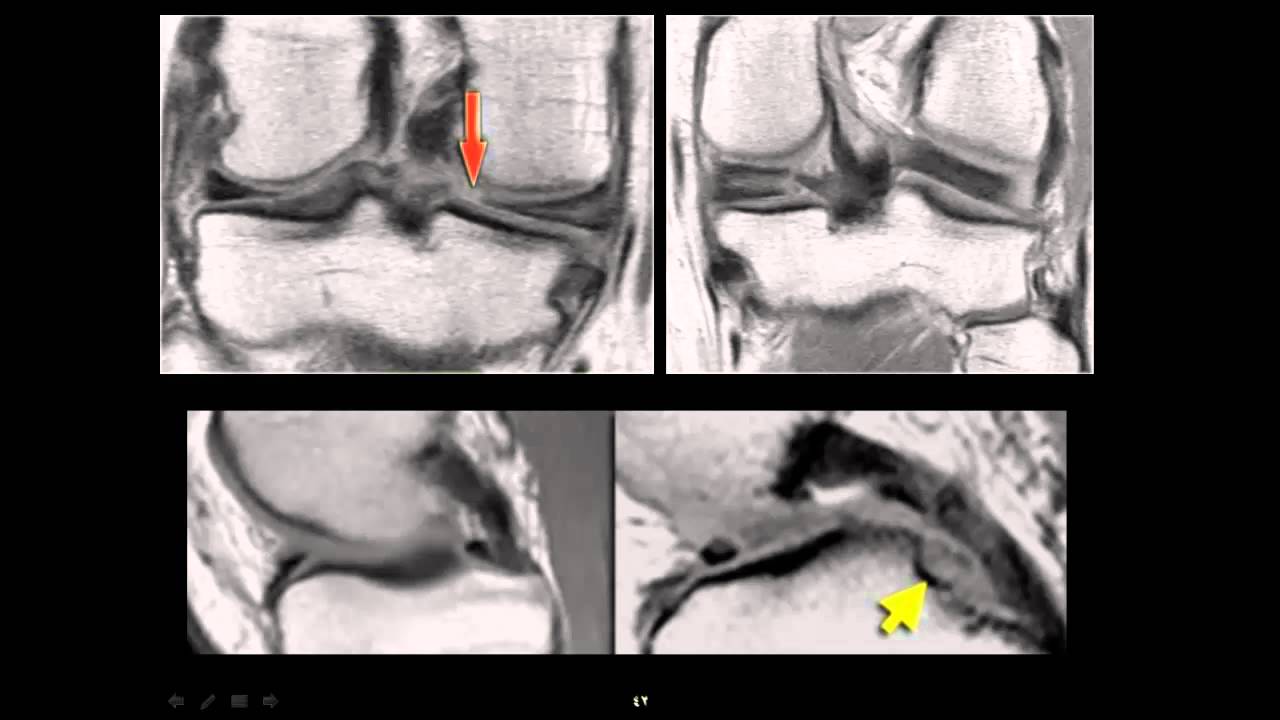

From www.youtube.com

How to Read Knee MRI of Radial Meniscus Tear Sports Medicine Knee Zimmer Knee Mri magnetic resonance imaging (mri) safety information for zimmer implants. That’s why the persona knee was. the size, shape, and fit of your knee implant can make a big difference in your satisfaction after total knee replacement. welcome to zimmer biomet. This protocol is applicable for the zimmer biomet psi and signature total and partial knee guides. Magnetic. Zimmer Knee Mri.